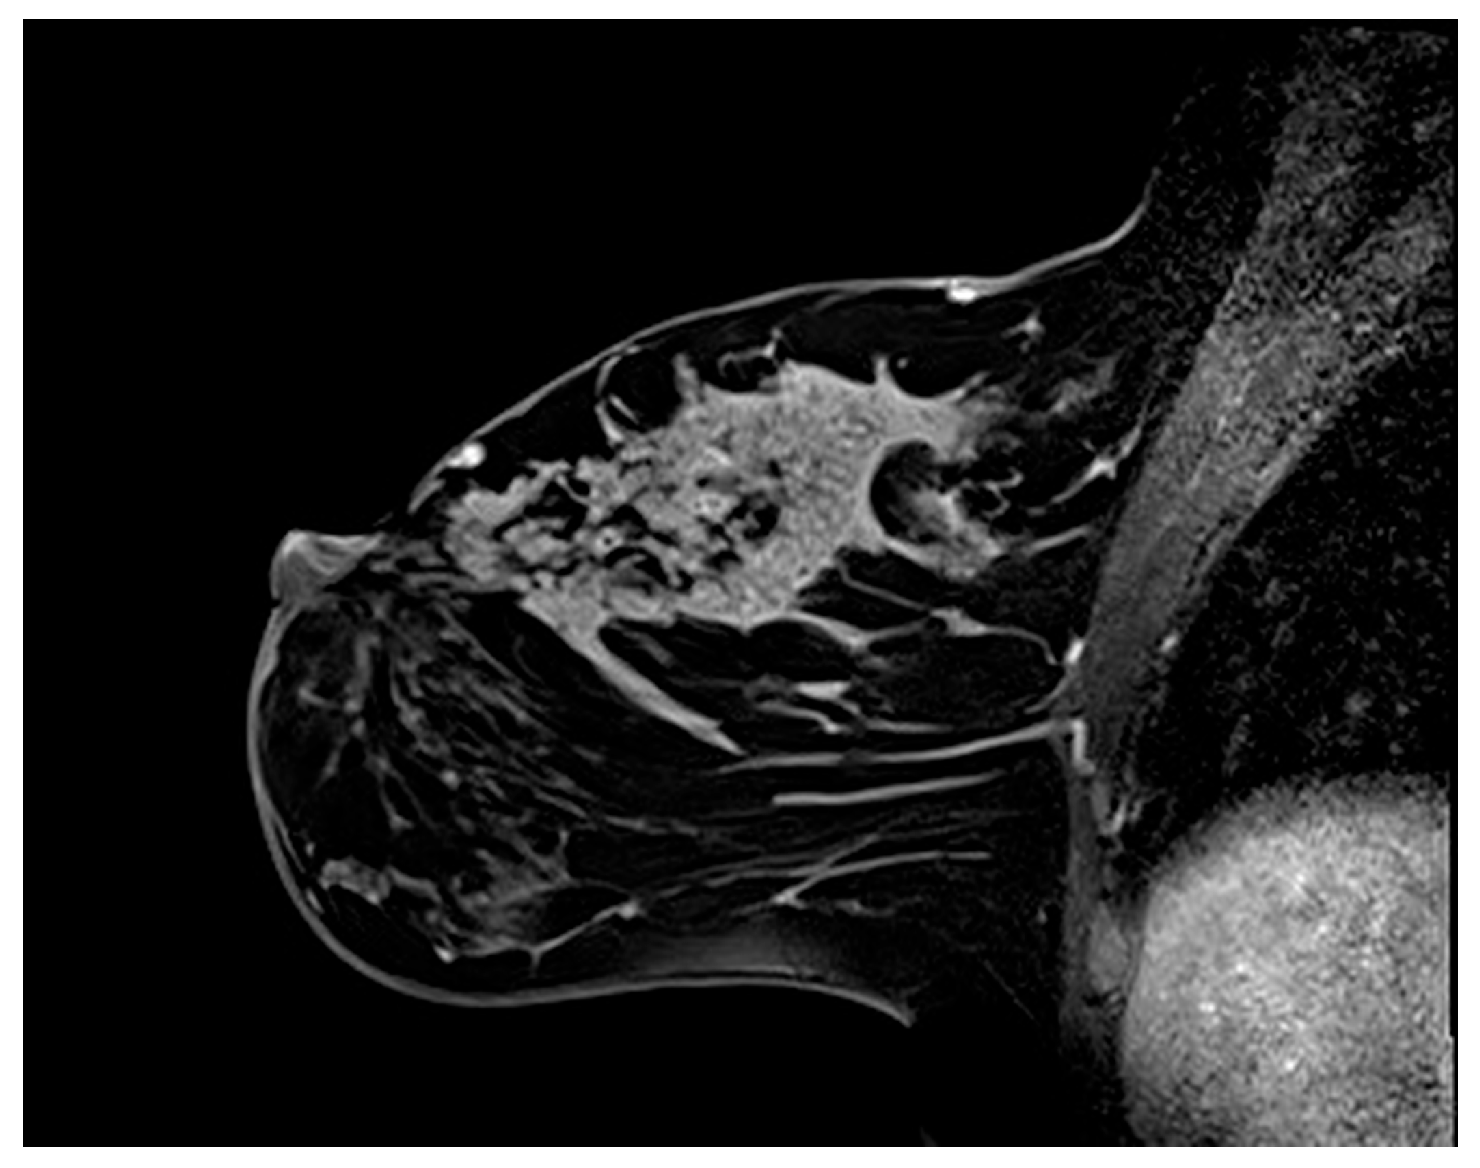

3.2.1. Internal Enhancement Patterns

3.2.2. Mixed Enhancement Patterns